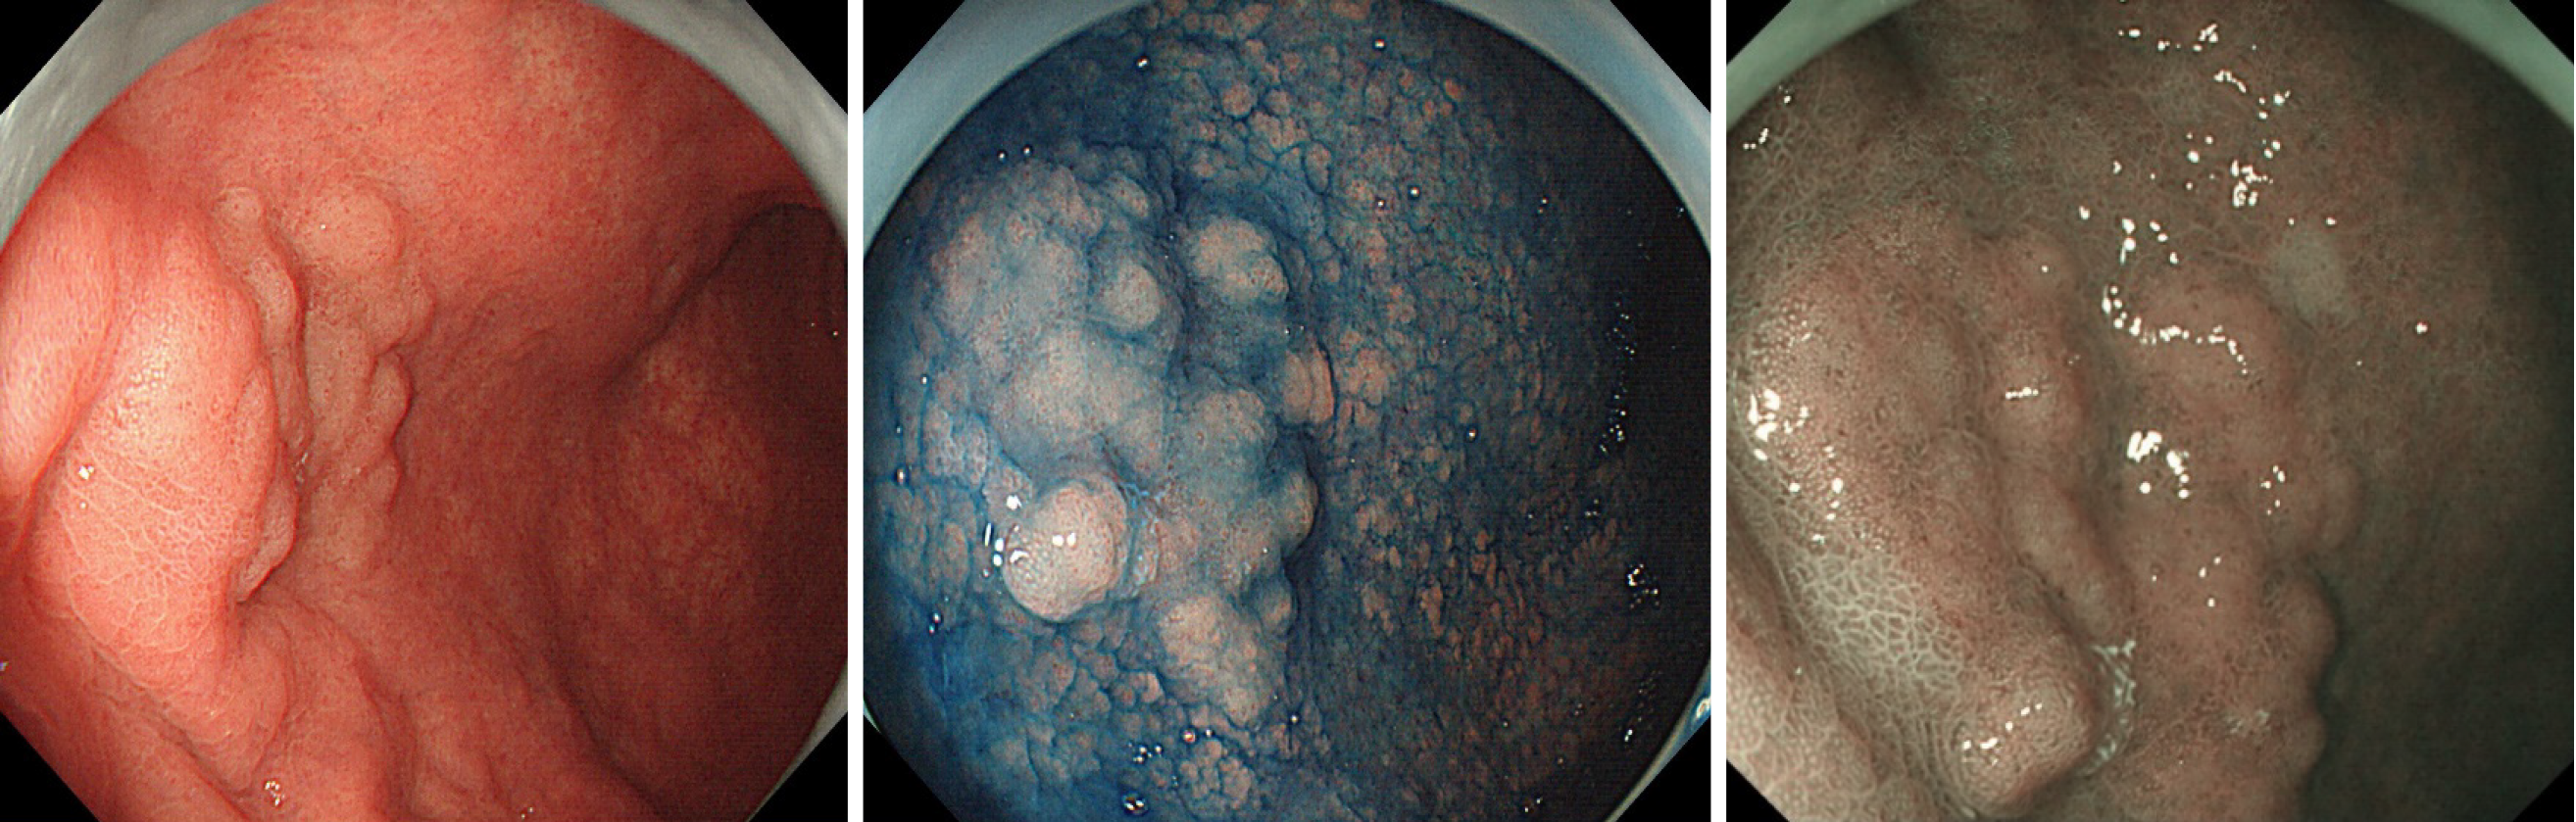

胃のMANET(2020年の報告) 通常の腺腫と同様にESDで根治されています